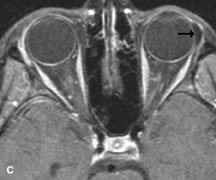

Metastatic Tumors

Breast carcinoma metastatic to the orbit has been demonstrated to be hypointense to the surrounding orbital fat on T1-weighted studies and hyperintense on T2-weighted images and has an affinity to the extraocular muscles (Fig. 20).50,64 The MRI characteristics of prostate carcinoma metastatic to the orbit have been described as involving the greater and lesser wing of the sphenoid, orbital roof, and optic canal. Diffuse bone hypertrophy with isointense or slightly hyperintense tissue on T1-weighted images represents the osteoblastic carcinomatous bone infiltration. Contrast enhancement is variable on T1-weighted and fat-suppressed images.65

Fig. 20. A. T1-weighted MR scan demonstrates nodular enlargement of both medial rectus muscles (arrows). B. T1-weighted fat-suppressed contrast-enhanced scan confirms the presence of small metnstatic deposits within the muscles (open arrows).